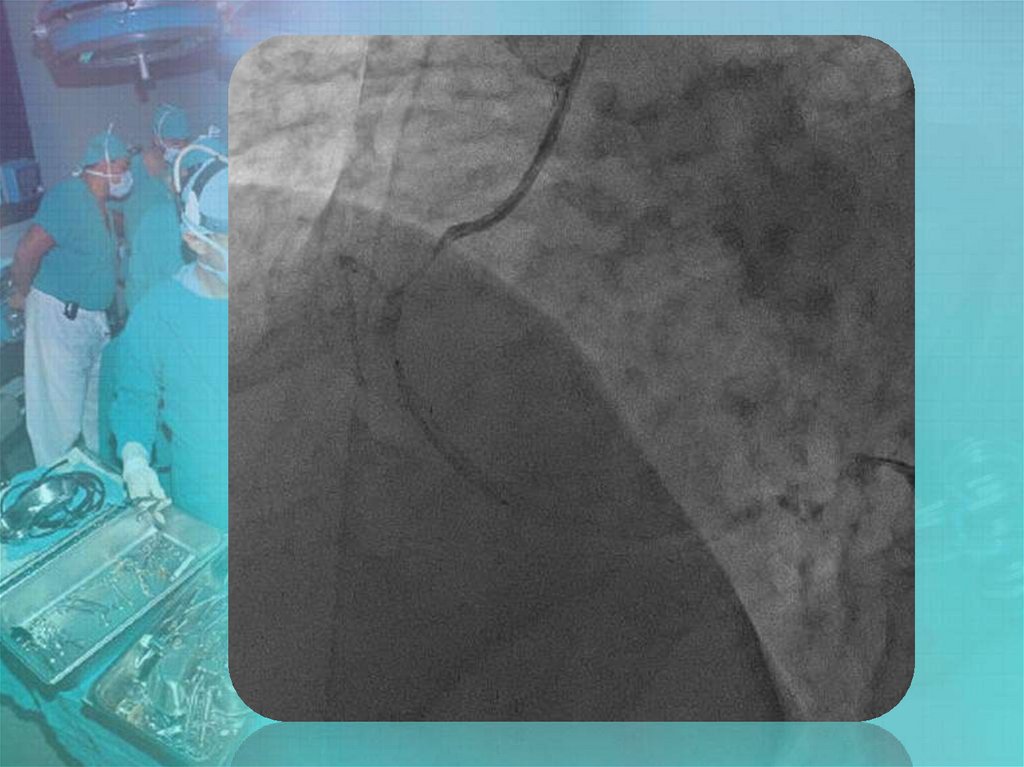

Коронары. СНК кафедры факультетской хирургии №2 лечебного факультета